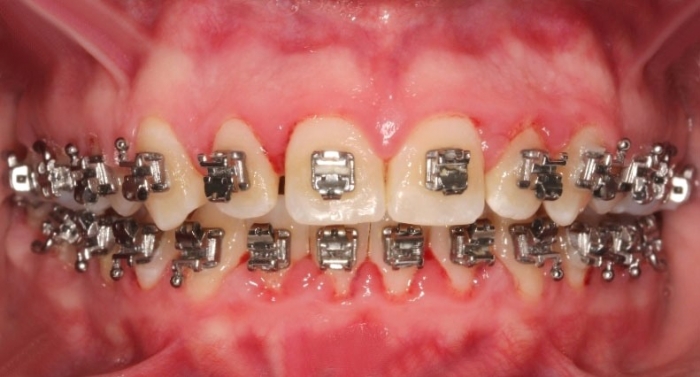

Oclusão após a cirurgia 2019